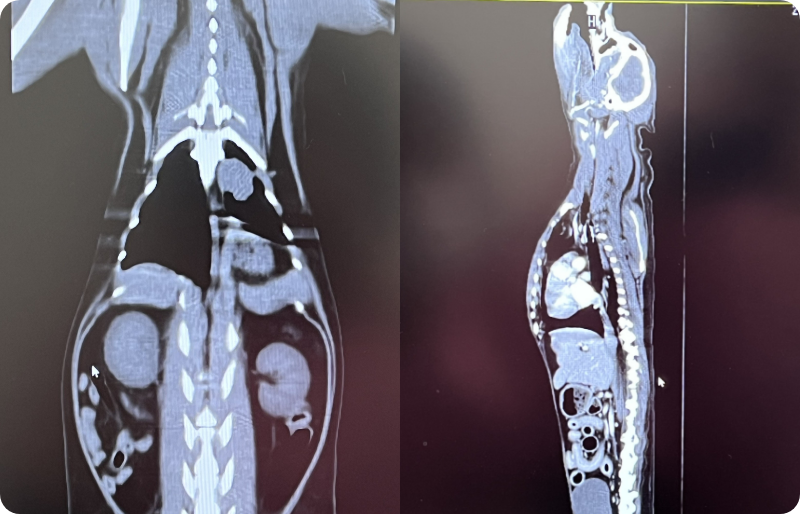

CT(コンピューター断層撮影)は、体の内部を輪切り状に撮影し、骨・内臓・血管などを立体的に確認できる画像検査です。

レントゲンやエコーではわかりにくい部分も、より詳しい情報が得られる場合があり、病気の早期発見や診療の判断材料として活用されます。

当院で導入予定の機器は16列マルチスライスCTで、一度に広範囲を撮影できるため、従来よりも短時間で検査が可能です。被ばく低減技術を搭載しており、低線量でも高精細(最小スライス厚0.625mm)の画像が得られます。撮影画像からは、任意の角度の断面像や3次元表示画像の作成も可能で、より詳細な検査が期待できます。